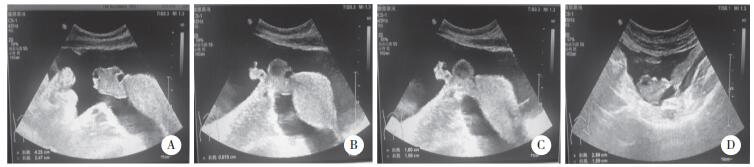

患者入院时一般状态欠佳,心率达120次/min,血压84/62 mmHg,体温36.6 ℃,呼吸16次/min。妇科查体:双附件区厚,子宫直肠窝空虚。完善实验室检查。血清肿瘤标志物:CA125 789 U/mL,HE4 156.3 pmol/L,其余肿瘤标志物未见异常。盆腔超声提示:右侧卵巢大小约4.2 cm×2.4 cm,形态欠规整,回声不均匀(图 1A),内见数个囊泡样回声,大者直径约0.92 cm,其内清晰(图 1B);右侧卵巢内还可见低回声,大小约1.8 cm×1.6 cm,未见血流(图 1C);左侧卵巢大小约2.5 cm×1.6 cm(图 1D)。全腹增强CT提示:双侧附件区生理性囊肿可能大(图 2)。炎症相关指标:C反应蛋白12.6 mg/L。其余检查发现,患者合并肺栓塞、下腔静脉和左肾静脉血栓不除外,胸腔积液,心包少量积液,低氧血症,低蛋白血症,离子紊乱(低钾、低钠、低钙),肾功能不全。给予患者吸氧、纠正离子紊乱、消炎、抗凝等一系列对症支持治疗。患者入院第2天腹泻加重,呈水样便,每日高达10余次,给予止泻治疗。患者因呼吸困难、腹胀难忍,遂行腹腔穿刺放腹水,标本送检未发现瘤细胞(图 3)。因患者目前存在多脏器损害和多浆膜腔积液等症状和体征,且我院的影像学检查和腹水化验均无法得到卵巢恶性肿瘤的诊断,故请风湿免疫科医生会诊,建议行风湿免疫相关生化检查。结果回报:抗核抗(+),1∶320,核颗粒型;抗SSA抗体(3+),抗SSB抗体(3+);抗Ro-52抗体(2+);单项补体C3 0.23 g/L,单项补体C4 0.01 g/L,红细胞沉降率66 mm/h。风湿免疫科会诊结果:除外妇科肿瘤和感染后,考虑SLE可能性大,建议转入风湿免疫科进一步诊治。患者和家属拒绝进一步诊治,患者于2020年11月5日因急性肺栓塞、呼吸衰竭死亡。

| A,水平面;B,C,冠状面. 图 2 全腹增强CT图像 |